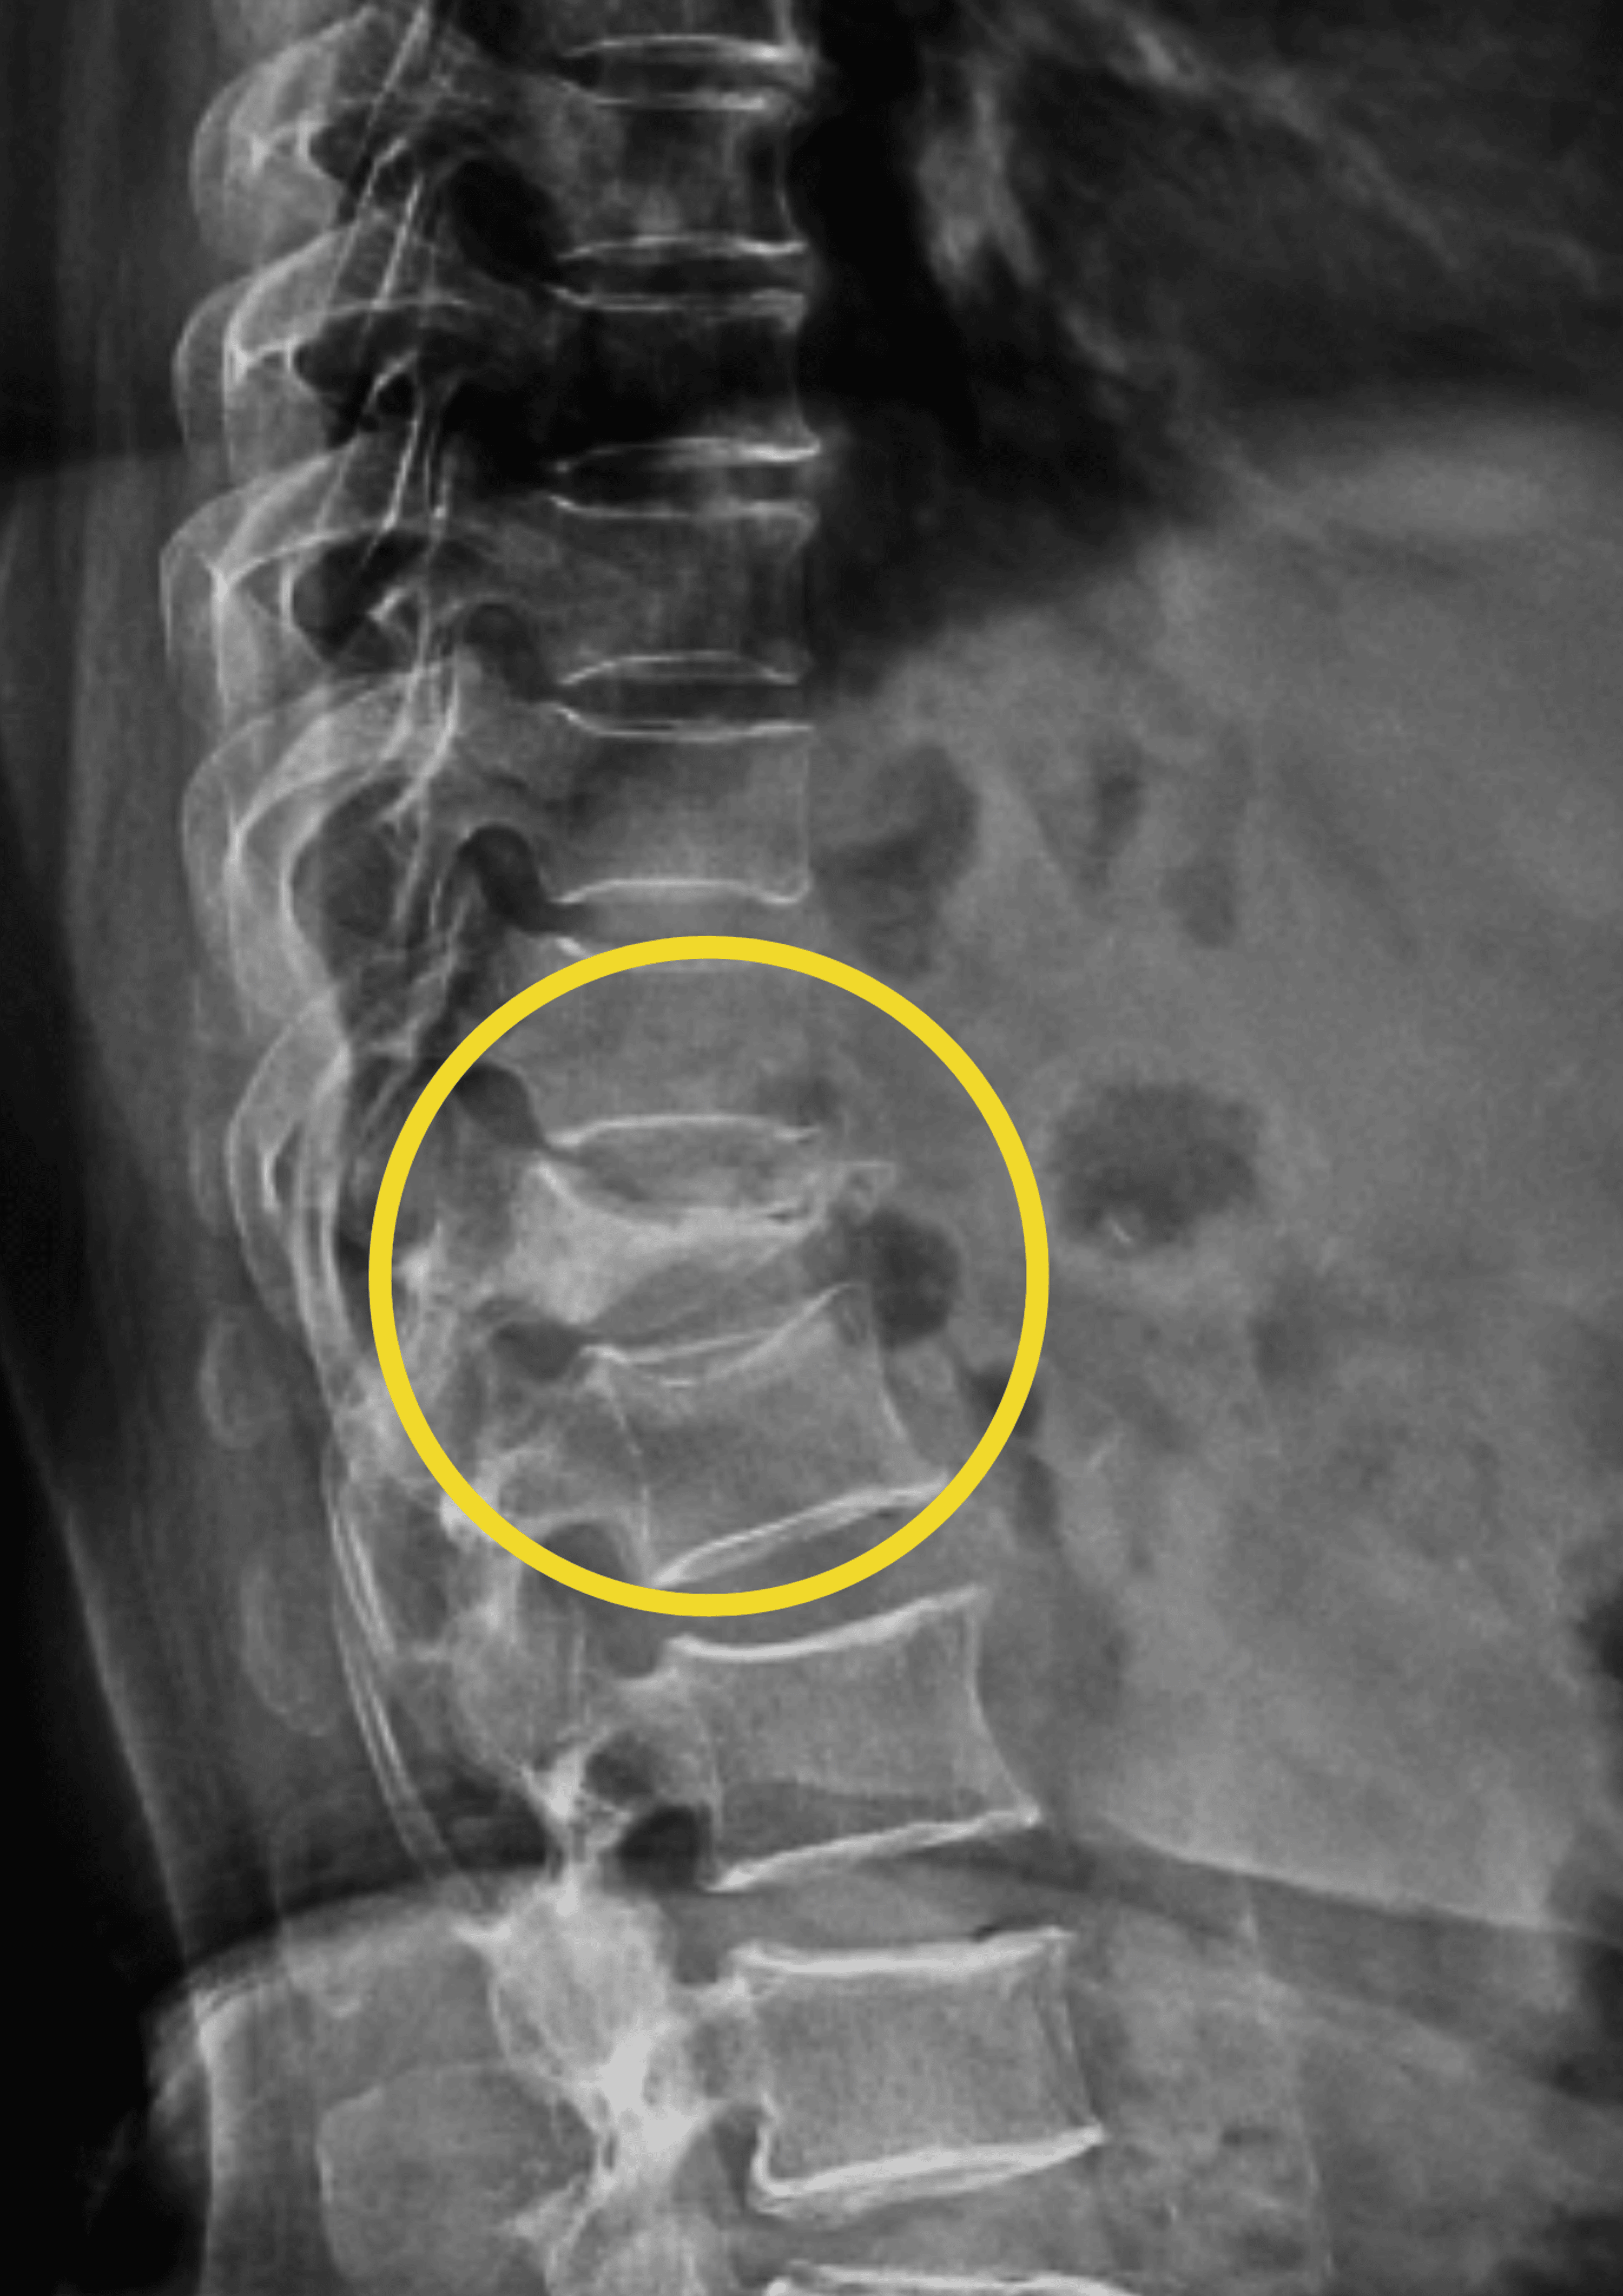

A Xray and B MRI pictures of an 81yearold lady after injury

A Xray and B MRI pictures of an 81yearold lady after injury Compression Fracture D12 compression fractures can result from osteoporosis, trauma or represent a pathological fracture secondary to another process (e.g. osteoporotic vertebral compression fractures are very common fragility fractures of the spine that affect up to 50%. pain from a spinal compression fracture allowed to heal naturally can last as long as three months. vertebral compression fractures (vcfs) of. Compression Fracture D12.

T2WI MRI dorsal spinesagittal view compression fracture of D12 Compression Fracture D12 vertebral compression fractures (vcfs) of the spinal column occur secondary to an axial/compressive (and to a lesser extent, flexion). compression fractures affect many patients worldwide and are most common in elderly populations, especially postmenopausal. osteoporotic vertebral compression fractures are very common fragility fractures of the spine that affect up to 50%. pain from a spinal compression. Compression Fracture D12.